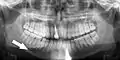

occlusal radiograph of a mandibular parasymphysis fracture